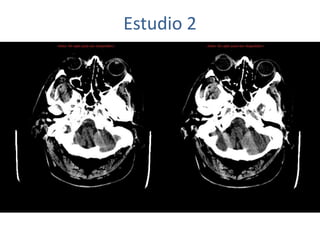

Estudio 2

• Estudio sin y con contraste, con reconstrucciones sagitales y coronales

del estudio con contraste.

Se observa una lesión ocupante de espacio en lóbulo frontal derecho que

presenta un tamaño de 18 x 32 x 22 mm (cc x ap x tr), bilobulada, no del

todo bien delimitada, con realce en anillo irregular, con hipocaptación

central, probablemente por necrosis, y asociada a un extenso edema

vasogénico con efecto masa tanto sobre los surcos de la convexidad

como sobre la cisterna insular, el sistema ventricular y la línea media,

esta última con un desplazamiento de 5 mm a la altura del septo

interventricular.

No se aprecian otras lesiones focales intra o extraaxiales de significación

patológica.

Habría que considerar como primera posibilidad que se tratase de una

lesión metastásica, por bien un tumor primario, aunque no se puede

descartar otras opciones, sin imprescindible correlación con la clínica y

con sus antecedentes.